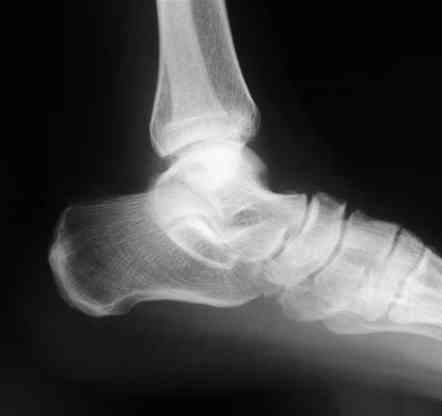

Лодыжку так ипрооперировал двумя 3.5 мм шурупами пришлось открыть - закрыто не удалось адекватно отрепонировать, при открытии - надкостничная

интерпозиция.

Я бы лодыжку зафиксировал двумя 3.5 или 4.0 мм лодыжечными шурупами, без смещения можно и закрыто, но это будеть видно во время операции.